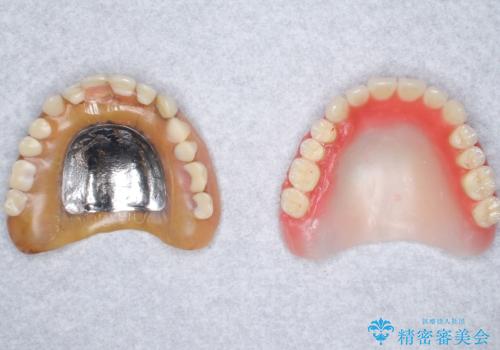

- 上の入れ歯の歯がとれてしまったこと・ゆるくてはずれてしまうことを主訴に来院された患者様です。

精査したところ、長年使用されていた入れ歯は劣化し、人工歯の脱離及び適合不良を認めました。

患者様のご希望により、上顎金属床義歯の新製を行いました。